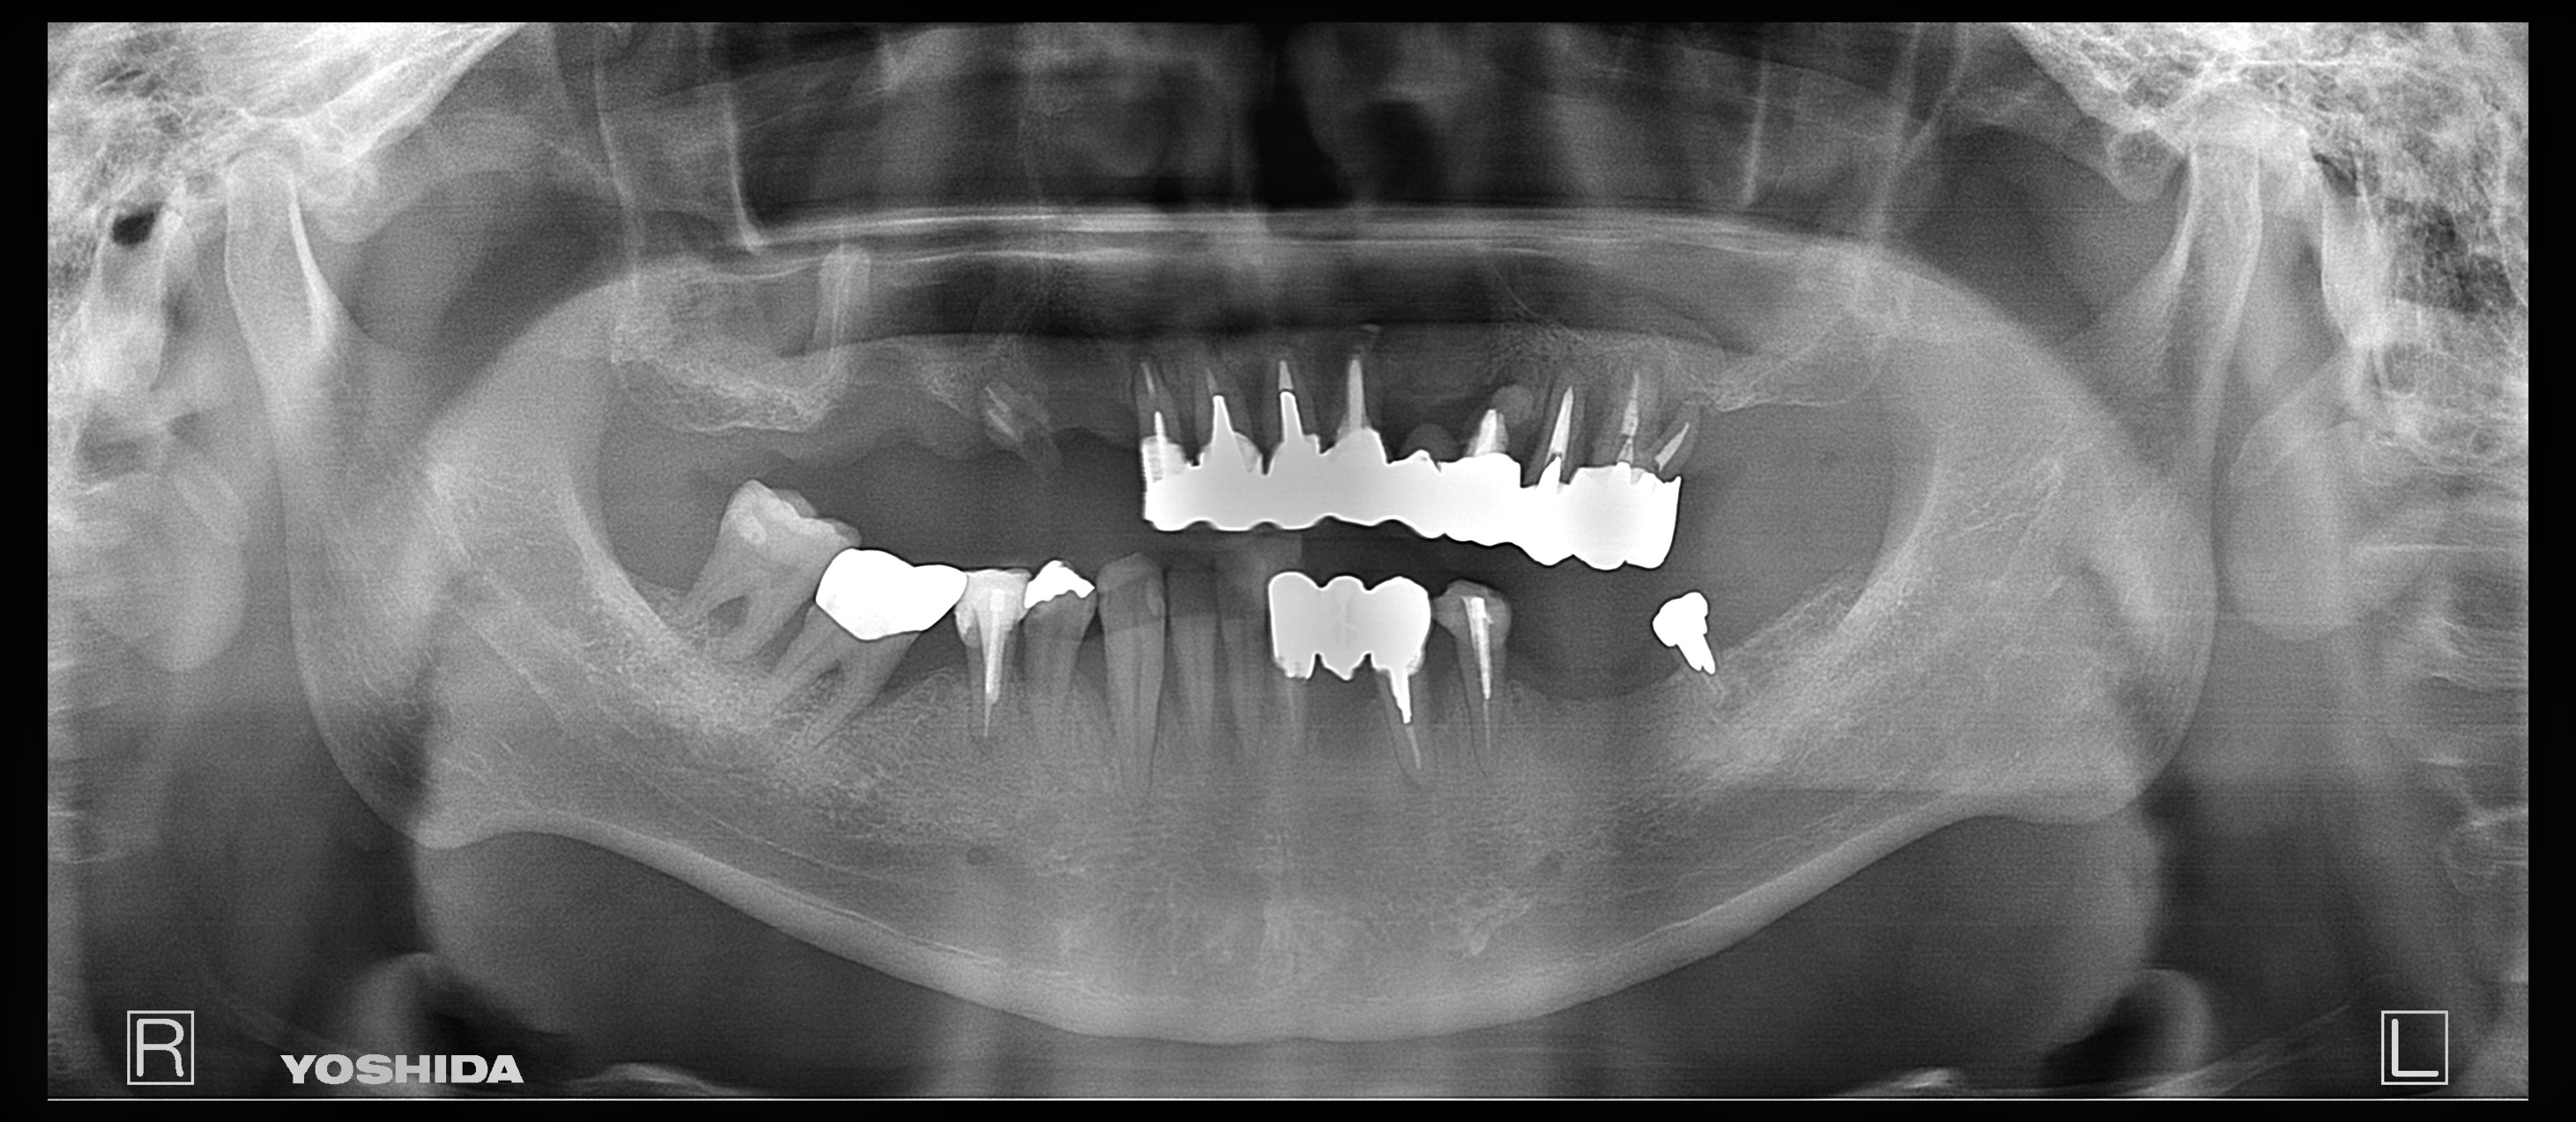

父のレントゲン写真と口腔内を見て、インプラントを入れる位置を一緒に決めて行きました。

右上は歯があるように見えて隣の歯につなげてある被せ物があるだけの状態です。

その右上は骨がないためサイナスリフトという処置を施した後にインプラントを入れる手術をしなければならないのですが、(サイナスリフトは骨を作るだけで6ヶ月待ちます。)

私は水口先生が開発したオステオプッシャーを用いて、骨がないところに骨を足す手術と並行してインプラントを入れる手術を施しました。

左側の入れ歯を入れていたと言っている場所には通常の方法でインプラント治療を、左上の奥歯2本は歯周病でグラグラだったため抜歯と同時にインプラントと治療を行いました。

左側のレントゲンがが最初の状態です。右側がインプラントを入れ、被せ物まで入れた状態のレントゲンです。